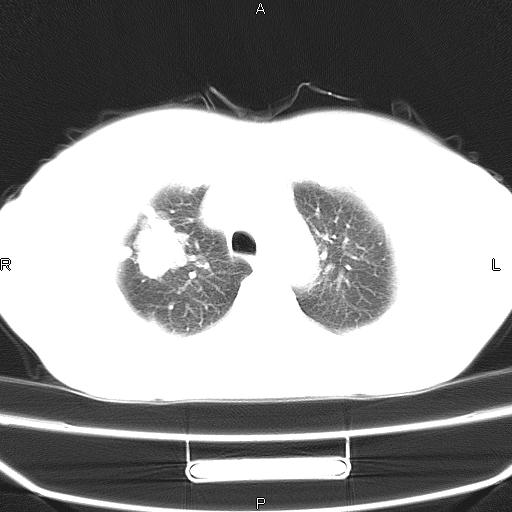

患者,女,66岁。健康体检胸部透视发现右上肺片状阴影。既往无不适,患者自诉三个月前曾有低热病史体温37.5左右一周。用药后缓解。至今无其它不适。请老师们指导指导。

考虑:右肺上叶周围型肺癌(分叶状肿块+砂粒状钙化+胸膜尾征)。

病灶见明显分叶、大小较大(大于3cm?),老年人,多考虑:肺癌,建议穿刺活检。

典型的中心型肺癌,尖段支气管阻塞。

周围性肺癌,

周围性肺癌可能性大,建议增强

右肺上叶周围型肺癌可能性大。

考虑:右肺上叶周围型肺癌